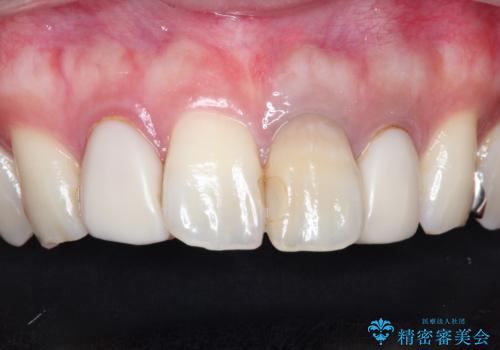

歯並びを含めて前歯をきれいにしたい インビザラインとセラミック治療

- 全体的なガタガタと前歯をきれいにしたいとのことで来院されました。

下の歯は重度のガタガタがあり、上の前歯は何本かが神経の治療がしてある状態でした。

インビザラインにて歯並びを整え、上顎の前歯にセラミックを装着する計画としました。

セラミックと矯正を組み合わせることにより、審美的にも機能的にも改善することができました。